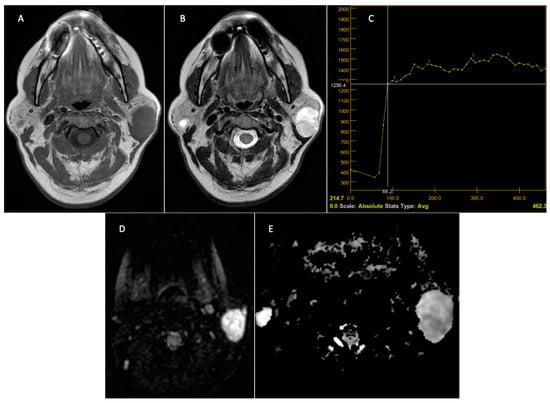

- Stoia, S.; Lenghel, M.; Dinu, C.; Tamas, T.; Bran, S.; Baciut, M.; Botan, E.; Leucuta, D.; Armencea, G.; Onisor, F.; et al. The Value of Multiparametric Magnetic Resonance Imaging in the Preoperative Differential Diagnosis of Parotid Gland Tumors. Cancers 2023, 15, 1325. [Google Scholar] [CrossRef]

- Yabuuchi, H.; Kamitani, T.; Sagiyama, K.; Yamasaki, Y.; Hida, T.; Matsuura, Y.; Hino, T.; Murayama, Y.; Yasumatsu, R.; Yamamoto, H. Characterization of parotid gland tumors: Added value of permeability MR imaging to DWI and DCE-MRI. Eur. Radiol. 2020, 30, 6402–6412. [Google Scholar] [CrossRef]

- Faheem, M.H.; Shady, S.; Refaat, M.M. Role of magnetic resonance imaging (MRI) including diffusion weighted images (DWIs) in assessment of parotid gland masses with histopathological correlation. Egypt. J. Radiol. Nucl. Med. 2018, 49, 368–373. [Google Scholar] [CrossRef]

- Coudert, H.; Mirafzal, S.; Dissard, A.; Boyer, L.; Montoriol, P.F. Multiparametric magnetic resonance imaging of parotid tumors: A systematic review. Diagn. Interv. Imaging 2020, 102, 121–130. [Google Scholar] [CrossRef] [PubMed]

- Elmokadem, A.H.; Abdel Khalek, A.M.; Abdel Wahab, R.M.; Tharwat, N.; Gaballa, G.M.; Elata, M.A.; Amer, T. Diagnostic Accuracy of Multiparametric Magnetic Resonance Imaging for Differentiation Between Parotid Neoplasms. Can. Assoc. Radiol. J. 2019, 70, 264–272. [Google Scholar] [CrossRef] [PubMed]